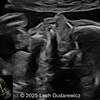

A 30-year-old G2P1, with an unremarkable history, presented to our office in the 21st week of her pregnancy for a routine second-trimester screening. Our examination revealed the following findings: